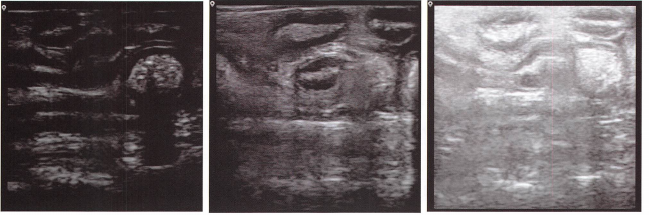

各器官扫查位置